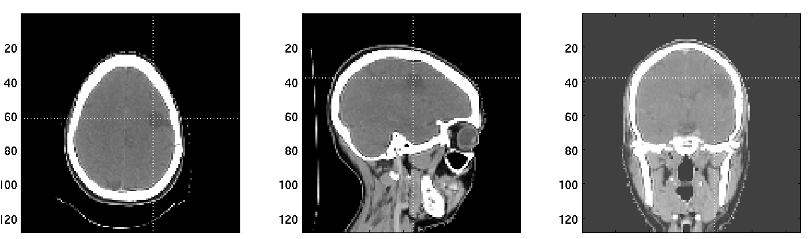

Because we now have 3D images, it is important to define imaging planes since we still view images in 2D slices.

The canonical orientations are axial/transverse, coronal, and sagittal.

Axial/transverse: cross-sections of the body, horizontal slices looking up from the feet. This is the most common view for CT images, although others are also used.

Coronal: view facing the subject.

Sagittal: view from the side of the subject

CT coordinates are typically as follows: Z from superior to inferior(head to feet), X from right to left (patient orientation), and Y from posterior to anterior (patient orientation). Images are typically displayed in transverse/axial, sagittal, and coronal views. Transverse are in the XY plane, coronal in the XZ plane and sagittal in the YZ plane. Transverse are cross sections of the body looking up from the feet, coronal are shown as if facing the patient, and sagittal are from the side of the patient. See imaging planes.